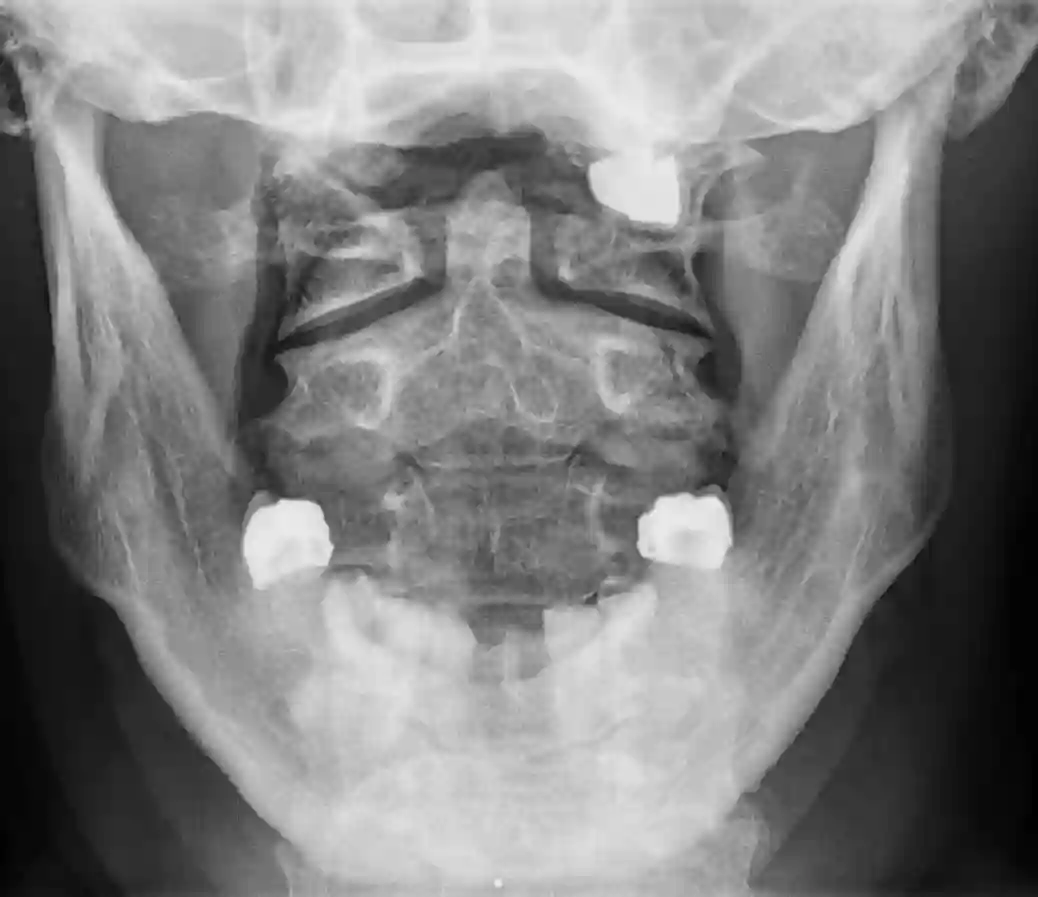

Dens Axis im Röntgen transoral

Darstellung einer transoralen Röntgenaufnahme eines intakten Dens axis im Röntgen.